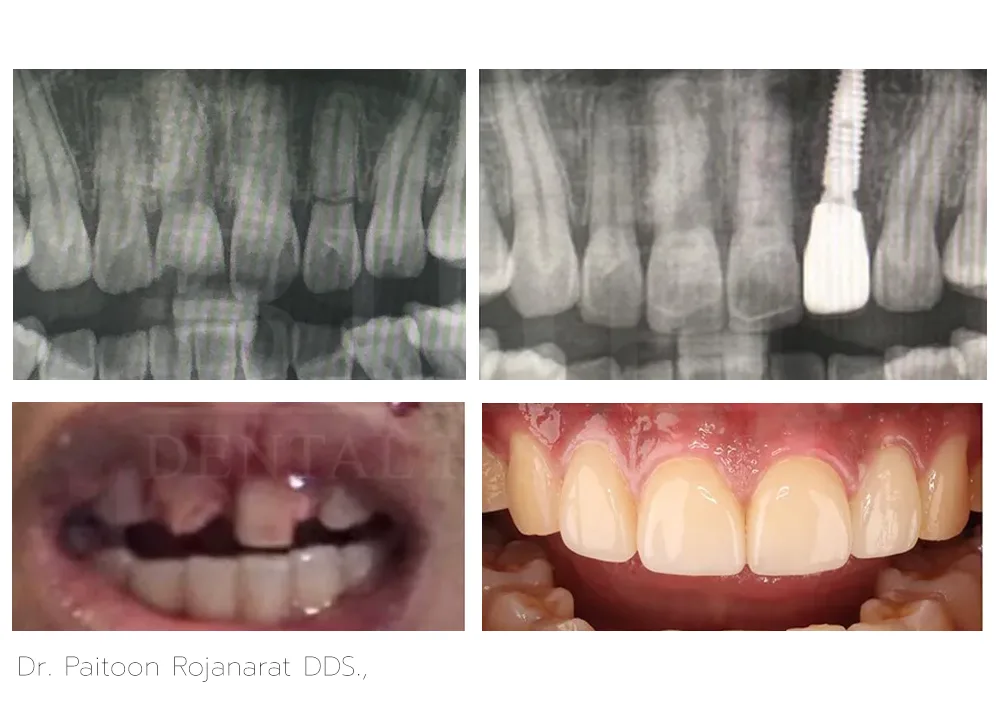

Dr. Paitoon Rojanarat DDS.,

Dr. Paitoon Rojanarat, DDS, is a dentist specializing on prosthodontics and esthetic dentistry that includes crowns, bridges, dental implants, veneers, and teeth whitening. With his highly-skilled and qualified expertise, he crafts custom-made fixed hybrid bridges over implants and dentures over implants designed for a natural appearance and a comfortable fit.